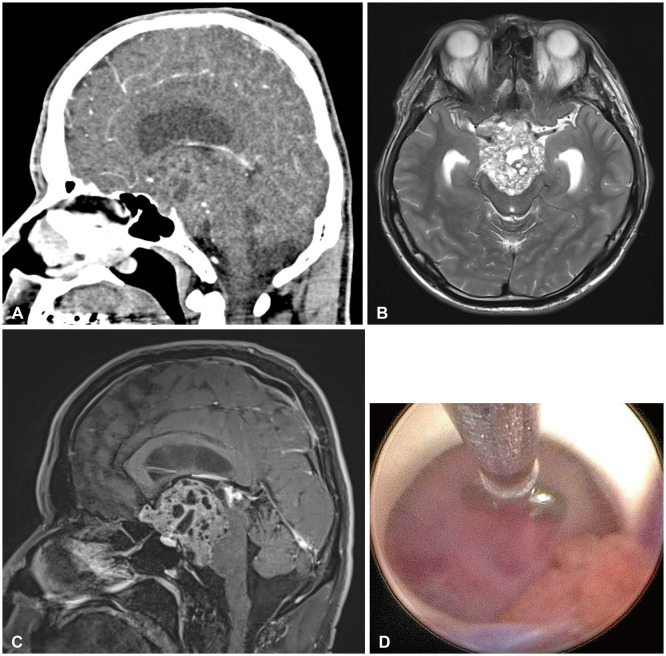

We report a rare and diagnostically challenging case of a 39-year-old male patient who presented with symptoms of dizziness and headaches, without any focal neurological symptoms. Initial imaging studies suggested a germ cell tumor, and an endoscopic biopsy led to a preliminary diagnosis of a pineal parenchymal tumor of intermediate differentiation. However, histological evaluation following surgical resection revealed the final diagnosis to be an ectopic pituitary neuroendocrine tumor (PitNET), a condition that is exceedingly rare. Ectopic PitNETs are uncommon tumors that develop outside the normal anatomical location of the pituitary gland. Their atypical presentation often leads to misdiagnosis as other intracranial neoplasms. This case highlights the diagnostic challenges posed by ectopic PitNETs and contributes to the limited literature on this rare condition. It underscores the importance of maintaining a broad differential diagnosis in patients presenting with atypical intracranial neoplasms.

Abstract Image